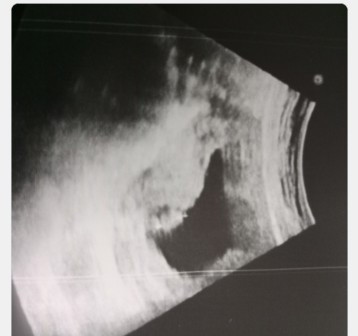

มีใครเจอเหตุการณ์แบบนี้บ้างคะ ไปฝากครรภ์ครั้งแรก ตอน8วิค หมอซาวด์บอกน้องได้3เซ็น พอไปซาวด์ครั้งที่2หมอบอกอาจจะท้องลม ไปรพ.หมอนัดตรวจอีกทีวันที่8 ควรทำใจไว้รึว่ายังไงคะ

8 วีค น้องไม่น่าจะถึง 3 เซนนะคะ .. หมอน่าจะหมายถึงขนาดของถุงตั้งครรภ์หรือป่าวคะ? ..หากรอบแรกเป็นขนาดถุงตั้งครรภ์ รอบ 2 ที่มาซาวด์ ก็มีโอกาสที่จะเป็นท้องลมค่ะ เพราะต้องเจอน้องโตขึ้น และมีสัญญาณหัวใจตั้งแต่แม่ซาวด์ครั้งแรกแล้ว